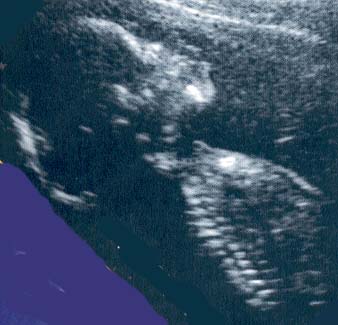

Here are a few sonar photos to illustrate the appearance of the fetus at different stages of a pregnancy.

This is a nine weeks pregnancy as seen using a vaginal probe.

Photo Three

This is a twelve weeks pregnancy as seen by external (through the abdomen) sonar.